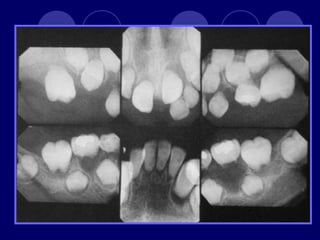

AMELOGENESIS IMPERFECTA  Hipoplásico: Zonas ausentes de esmalte  Afecta más a caras vestibulares  Esmalte: blanco amarillento y marrón claro, consistencia dura, fosas y surcos oscuras, delgado  Hipocalcificado:  Cualitativo  Esmalte frágil, fácil de desprender  Rx: falta de contacto entre dentina, esmalte  Hipomaduro:  Disminución en el contenido mineral  Esmalte blando y rugoso, veteado de blanco a marrón (esmalte en copos de nieve)  Más frecuente en caras vestibulares y dientes superiores